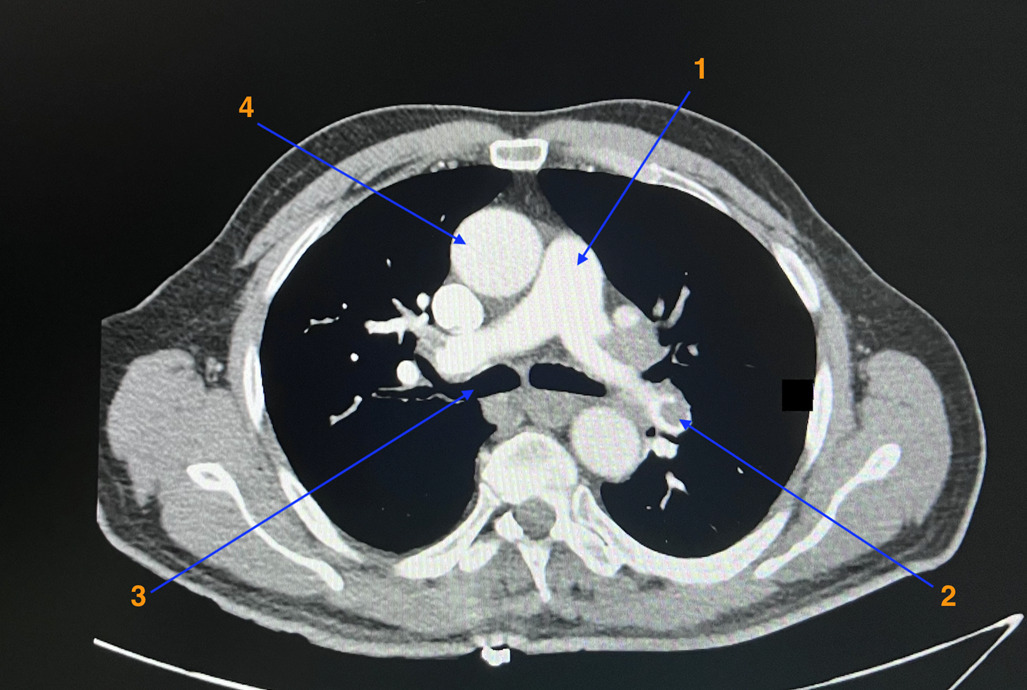

Oui, douleur évocatrice, antécédent de TVP, dyspnée.

Toujours y penser mais la douleur n’est pas typique, la tension est symétrique ainsi que les pouls périphériques n’expliqueraient pas la dyspnée.